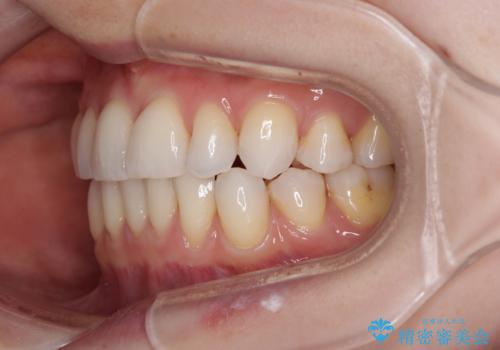

アンカースクリューを用いて正中位置を調整したことで、上下の正中位置をほぼ一致させることができました。

移動量が多かったため、治療期間は長くなりましたが、大変満足のいく仕上がりとなりました。